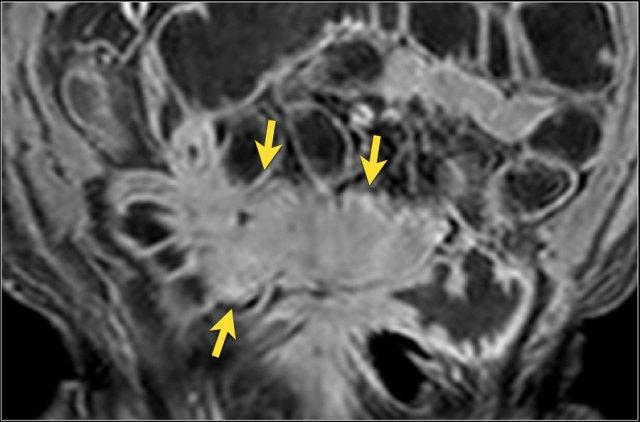

Bệnh nhân nữ 48 tuổi, đang điều trị bằng thuốc kháng TNF, được chỉ định nội soi đại tràng.

Phát hiện hẹp lòng ruột ở đại tràng sigma, không thể vượt qua được khi nội soi.

MR-enterography được thực hiện để đánh giá mức độ lan rộng của chỗ hẹp.

Ruột non bình thường, nhưng ghi nhận các đoạn hẹp ở đại tràng xuống và đại tràng ngang.

Cả hai đoạn hẹp đều có thành ruột dày đến 8 mm và ngấm thuốc rõ rệt theo kiểu niêm mạc ở đại tràng xuống và kiểu phân lớp ở đại tràng ngang.

Giãn ruột trước chỗ hẹp được ghi nhận ở cả hai đoạn.

Do các chỗ hẹp này không hiện diện khi nội soi đại tràng trước khi điều trị kháng TNF, nhiều khả năng chúng đã hình thành trong quá trình điều trị.

Do đó, quyết định phẫu thuật cắt đại tràng gần toàn bộ với miệng nối hồi-sigma đã được đưa ra.